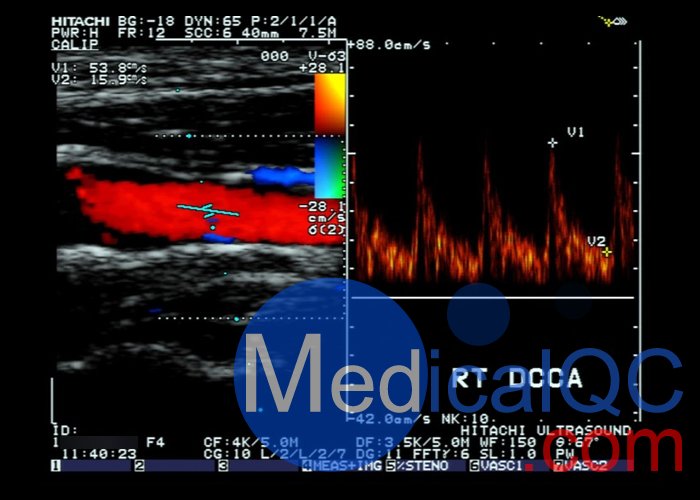

包括波形:成人頸總動脈,頸動脈狹窄,股動脈,主動脈。胎兒大腦中動脈,腎動脈,臍動脈。小兒降胸動脈,動脈導管未閉。

測試波形:峰值速度為100,150和200厘米/秒的正弦波。三角波峰值速度為100,150和200厘米/秒。停止在0,20,40,60,80和100厘米/秒的階梯波。